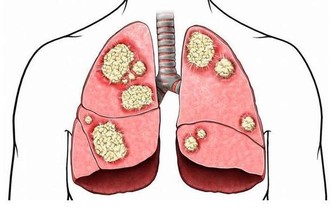

白髮的產生,不只是一種老化現象,也跟情緒、壓力相關。在人體毛囊中,有一種黑色素細胞,能夠合成真黑色素、褐黑色素,亞洲人的毛囊中有高濃度的真黑色素,這是為什麼毛髮會是黑色的原因,至於西方人的髮色較淺,則是因為有褐黑色素濃度較高,以及真黑色素濃度較低,因此出現紅色、棕色、金色的髮色。

當毛囊內的黑色素細胞發生退化,就無法再製造黑色素,於是產生白髮。